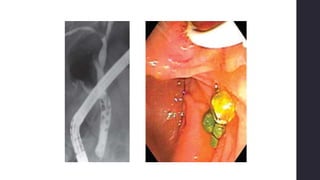

CPRE – GS (dx y

tx)• Enfinterectomía endoscópica + extracción del cálculo

⚫50% recurrencia (sin colecistectomía)

• Mortalidad <1%

• Complicaciones 5-10% (hemorragia, pancreatitis, conlangitis,

perforación retroduodenal)

*Cálculos de gran tamaño (>2cm), intrahepáticos, múltiples,

alteración de la anatomía gástrica o duodenal, cálculos impactados

y divertículos duodenales

endoscópicosCPRE + esfinterectomía endoscópica

o Éxito >90%

o Morbilidad: 5-9.8%

o Mortalidad: 0.3-

2.3%

Canastilla de Dormia

Procedimientos

endoscópicos

Dilatación endoscópica con balón

- Minimiza el daño del esfínter

- Sumado a esfinterectomía mínima

- Pacientes con riesgo de sangrado